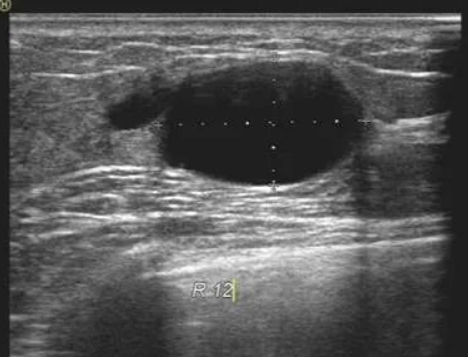

B超检查结果一般由典型图像、乳腺结构的描述和超声诊断三部分组成,主要报告里面会描述乳腺内部有无异常的回声、大小、形状,导管是否扩张?腋窝淋巴结的情况。

首先需要看结节的大小和形状,如果结节比较小,形状规则,边界清晰,一般是良性的,可以3-6个月随访观察;如果边界毛糙,欠清晰,形态不规则,呈“螃蟹足”的改变,那么恶性的可能性比较大。

规则、椭圆形的良性肿瘤